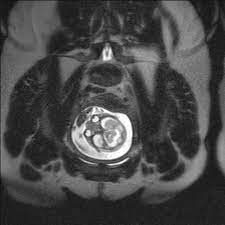

fetal mr goruntuleme yararli bilgiler guney emar